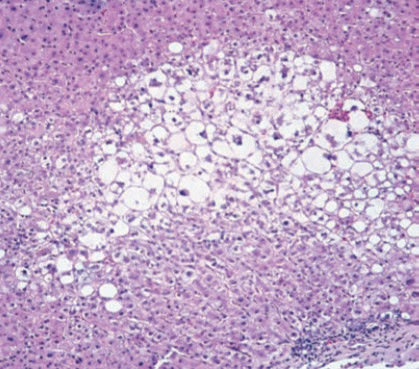

phosphatase, and bilirubin are all elevated. A liver biopsy

demonstrates alcoholic hepatitis with Mallory bodies. These

cytoplasmic structures are composed of interwoven bundles

of which of the following proteins?